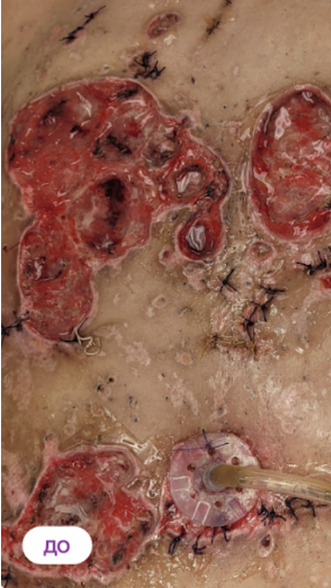

Гидраденит, осложненный СД 2 типа или инверсное акне

Пациент проходил несколько эпизодов хирургического лечения, но появляются новые очаги, воспаляются старые. К антибиотикам и народной терапии чувствительности нет. Вся картина вызвана и осложняется наличием сахарного диабета 2 типа, что сильно подкашивает иммунитет (диабет декомпенсированный) + низкая заживляемость и затянувшийся воспалительный процесс.

Назначено: 1 сеанс ФДТ REVIXAN

Параметры изменяются в зависимости от процедуры

Дата публикации: 22.08.2025 14:33:53